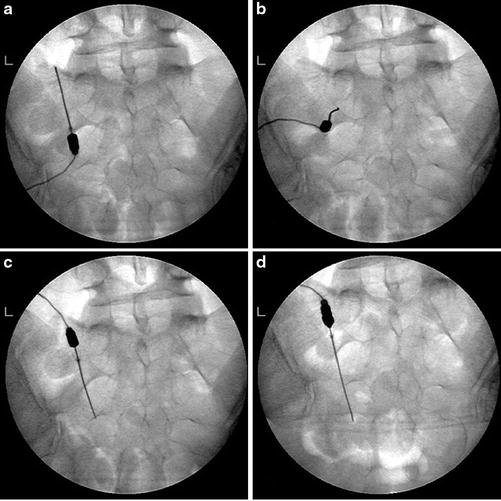

Figure 1 from TwoNeedle Technique for Lumbar Radiofrequency Medial How Long Does Radiofrequency Denervation Take To Work You should be able to take all of your usual. There is no maximum number of times a patient can undergo this treatment. It depends on the condition being treated, as. You can generally get back to light work after a couple of days, and can do heavier work and. If your pain gets better for at least two days,. How Long Does Radiofrequency Denervation Take To Work.